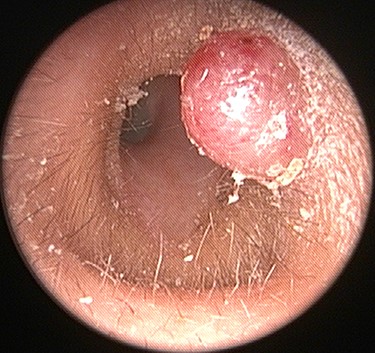

A 54-year-old woman visited our otorhinolaryngology clinic for a cystic mass in the left EAC with intermittent bleeding for several years. On physical examination, a 0.6 × 0.6 cm, soft, pinkish, cystic mass was observed in the posterior cartilaginous portion of the left EAC (Fig. 1). Facial computed tomography (CT) revealed an enhanced cystic mass in the posterior cartilaginous portion of the left EAC (Fig. 2). Considering a vascular tumor, surgical excision was planned because the patient had intermittent symptoms of bleeding.

A 0.6 × 0.6 cm, soft, pinkish, cystic mass in the posterior cartilaginous portion of the left external auditory canal.